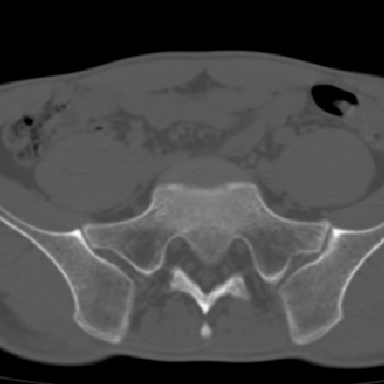

m 30 腰背部不适半年; 清晨时僵硬; 活动症状有所改善

双侧骶髂关节下2/3关节面模糊,毛糙,可见小囊状骨质破坏区.支持强直性脊柱炎.

强直性脊柱炎的早期改变!不仅表现为双侧骶髂关节,第5腰椎与骶椎间的关节突关节也有类似改变。

双侧骶髂关节下2/3关节面模糊,毛糙,髂骨侧可见小囊状骨质破坏区,骶髂关节间隙增宽(软骨破坏期)。支持早期强直性脊柱炎。

双侧骶髂关节下2/3关节面模糊、毛糙,可见小囊状骨质破坏区,呈虫咬状改变,周围可见增生硬化.支持强直性脊柱炎早期表现.

双侧骶髂关节髂骨面硬化,毛糙,小囊变,属于早期强直性脊柱炎